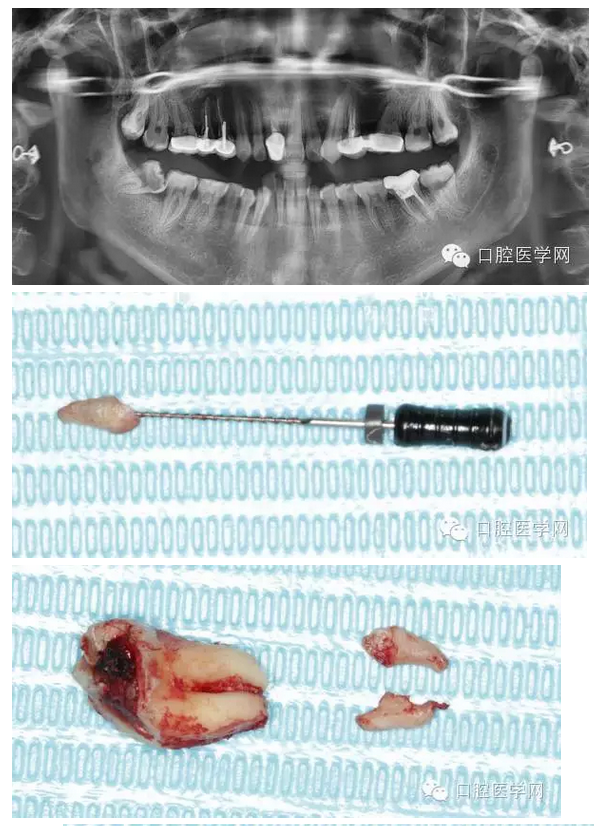

檢查發(fā)現(xiàn)右下8近中前傾阻生,合面大面積齲壞。拍全景片顯示右下8根尖向近中彎曲,右下7遠(yuǎn)中有淺齲,遠(yuǎn)中頸部有骨缺損。

告知拔牙斷根的可能性非常大,但是我會(huì)盡力拔除干凈,患者同意。

拔牙過(guò)程就不贅述了,果然斷根了,于是用40號(hào)H銼插入牙根斷面的根管口里,并盡量擰緊,然后拔出。最近好像買(mǎi)不到碧藍(lán)麻,只有斯康杜尼,局部浸潤(rùn)麻醉后出血明顯,嚴(yán)重影響操作,為了找根管口,擦拭了N個(gè)小棉球,讓人不堪忍受!讓人懷念的碧麻啊!